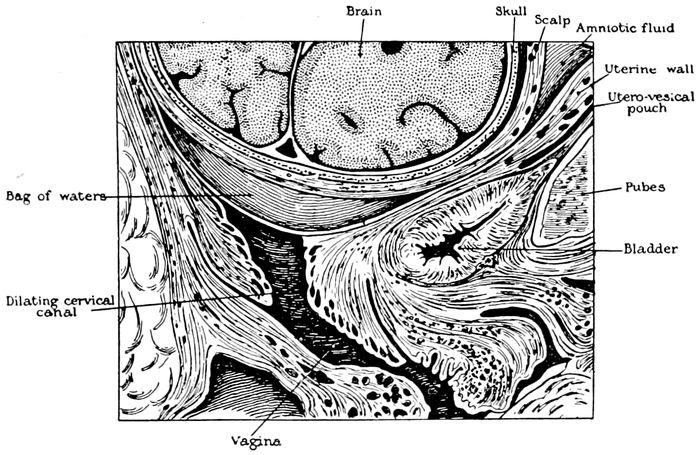

The bag of waters begins to act on the cervix |

111 |

| |

| 36. |

The effect of the pains. The cervix before labor begins |

112 |

| |

| 37. |

The effect of the pains. The cervix begins to be “effaced” |

112 |

| |

| 38. |

The effect of the pains. The cervix is effaced, and the dilatation of the os begins |

113 |

| |

| 39. |

The effect of the pains. The cervix is effaced and the os continues to dilate |

113 |

| |

| 40. |

The cervix is effaced and the os dilated |

115 |

| |

| 41. |

Child in second stage of labor |

116 |

| |